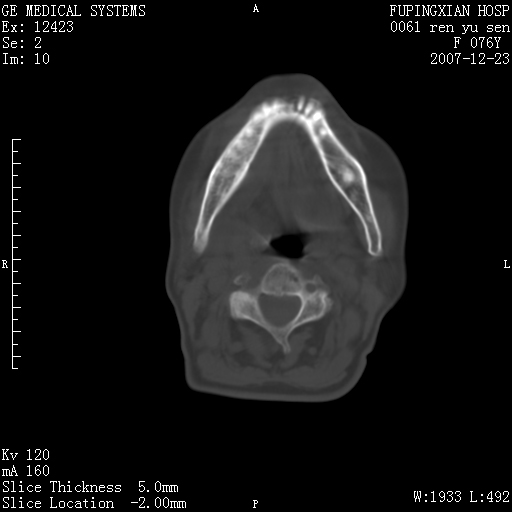

男性 76岁 下颌右侧磨牙区肿物数月, 约2.0*1.5cm大小波及颊舌侧,伴颌下淋巴结肿大。余(-)

右颈部颌下腺前可见一类圆形软组织密度影,密度不均,内见小片坏死区.颌下颈前可见两枚肿大淋巴结影.考虑淋巴结感染可能性大,建议增强扫描..

右侧第四磨牙缺失,局部牙槽骨质破坏,边界欠清晰,同侧颌下及竟不见多发肿大淋巴结显示。考虑肿瘤病变可能性大,感染待排